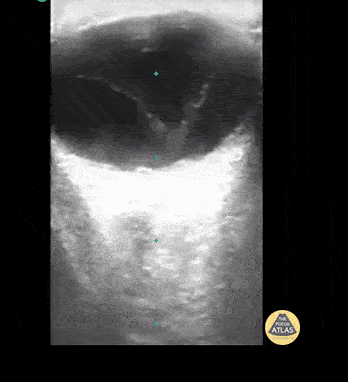

12 y/o with blurry vision for 1 month. POCUS shows thickening of vitreous in middle of eye / vitreous detachment. Note there is no point of fixation at the base/optic nerve when patient is asked to move eye side to side. This finding differentiates vitreous detachment from retinal detachment. Contributor: Rahul Shah, MD